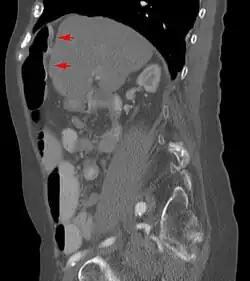

Chilaiditi-Syndrom in der Computertomographie sagittal

Das Syndrom ist eher selten (unter 1 %) und wird meist als Zufallsbefund auf Röntgenaufnahmen der Lunge, im Computertomogramm des Oberbauches oder im abdominellen Ultraschall erkannt. Bei Eingriffen an der Leber, insbesondere bei Leberpunktionen, ist die Kenntnis dieser anatomischen Variante von großer Wichtigkeit.

Es sind Anteile des Dickdarms – vor allem seine rechte obere Biegung (die Flexur) – oder seltener des Dünndarms zwischen den rechten Leberlappen und das rechte Zwerchfell verlagert. Das Syndrom kann mit Fehlbildungen der Leber, des Zwerchfells oder Dickdarmes einhergehen.